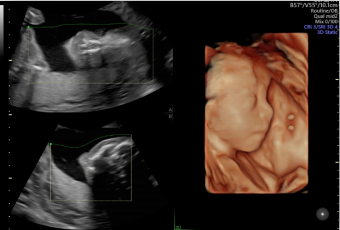

智能NT和智能IT

胎兒頸后透明層/顱內(nèi)透明層標準化測量,減少主觀因素差異。